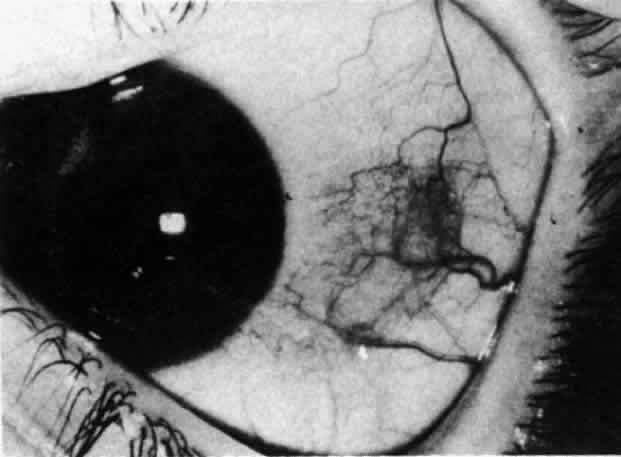

The object of slit lamp examination is to determine the depth and nature of scleral and episcleral conditions and the presence of corneal changes. The changes seen are drawn in the records. With the use of diffuse light with a neutral density filter, the vascular networks of both eyes are examined in detail to determine the layer in which the vessels show maximum congestion, the infiltration of episcleral tissues, and the edema of sclera, episclera, or subconjunctival space. Slit lamp examination is also used to ascertain the nature and depth of any corneal changes; the presence of scleral edema (for which it may be necessary to blanch the superficial tissues with epinephrine 1:1000 or phenylephrine 10%); the nature of any episcleral infiltration or mass; and the presence of cells in the anterior chamber or vitreous and posterior synechiae. The red-free (green) filter is extremely valuable in confirming the areas of maximum congestion and whether any areas are totally avascular. Because this is an important physical sign and is easily missed, examination in red-free light should be routinely performed. The green light brings the vessels into very sharp contrast with the background and enables the position of maximum inflammation to be determined with certainty. It also enables the paths and configurations of the vessels to be followed and will show lymphocytic infiltration of the episcleral tissue as yellow spots; this often indicates that the condition is more extensive than previously supposed (Fig. 8).

Fig. 8. Examination in red-free light. Blood vessels brought into sharp contrast reveal areas of lymphocytic infiltration in episcleral tissues, in this case due to herpes simplex virus.